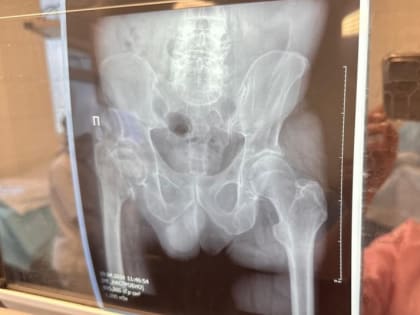

Высокотехнологичную помощь пациентам оказывают по полису ОМС Краевая клиническая больница имени профессора Владимирцева увеличивает количество операций по эндопротезированию тазобедренных и коленных суставов,